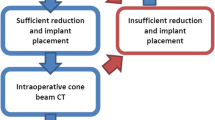

In 107 procedures, additional 3D-imaging was performed; most often once (84%), but sometimes two or three times during the surgical procedure. Most procedures with 3D-imaging were performed from the beginning of the year 2007. After 2007, a 3D scan was performed in 67% of the surgical procedures. Ninety percent of the scans were obtained after reduction and fixation, while the remaining 10% was performed after fracture reduction but before definitive hardware implantation. When 3D-imaging was available, in more than half (53%) of the operations an additional correction was performed following 3D-imaging. In contrast to corrections following 2D-imaging, 96.2% of the corrections were corrections of implant (plate and/or screw) position.

In this study, we found that when 3D-imaging is available at the surgeon’s preference additional corrections were performed in 53% of the patients, which were not performed after 2D-imaging. In addition, when the surgeon has 3D-imaging at his disposal the number of corrections performed after 2D-imaging decreases with 15%. These additional corrections are probably conducted because the increased information 3D-imaging gives about fracture reduction and implant position. However, the reduction in corrections performed after 2D-imaging also suggests that the surgeons’ attitude towards 2D-imaging changes unwittingly when 3D-imaging is also available: they tend to rely more on 3D-imaging and postpone their decision to correct until 3D-imaging has been performed.

Additionally, following 3D-imaging most of the corrections were performed because of a suboptimal implant position, while after 2D-imaging corrections of both reduction and implant position were performed. A reason for this difference could be that reduction can be evaluated adequately with 2D-imaging, while implant position is more difficult to evaluate based on these images. Another explanation could be the timing of 3D-imaging, which is most often at the end of the procedure. The threshold to optimize reduction at this stage of the procedure could be higher, because mostly different implants need to be removed. The threshold to revise only one or more screws because of length or position is lower and could therefore be done more frequently. The number of corrections in our study is slightly higher than the approximately 40% correction rate found in previous studies [12, 20]. However, the higher correction rate of implant position as found in the present study was also shown by others [15, 20].

Follow-up of a multicenter randomized trial is ongoing to answer the question whether the use of additional 3D-imaging improves the quality of reduction and fixation and patient outcomes [17]. In this study, the availability of intra-operative 3D-imaging is determined by randomization, not until the surgeon is satisfied about the reduction and fixation based on fluoroscopic 2D-imaging and is ready to end the operation. Radiologic outcome is determined as well as functional outcome by patient-rated outcome measures. The results of this trial are expected in the summer of 2017.